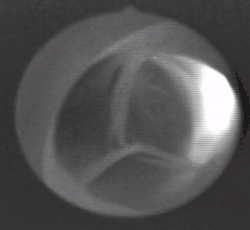

Každá poloměsíčitá chlopeň je tvořena obvodovým vazivovým prstencem, na který se zevnitř upínají tři kapsy poloměsíčitého tvaru. Kvůli nim je prstenec trojitě zakřivený (podle průběhu na něm upnutých kapes). Poloměsíčitá chlopeň v levé komoře se označuje jako aortální chlopeň (valva aortae), v pravé komoře je plicnicová chlopeň (valva trunci pulmonalis).[3]